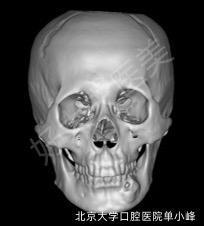

頜骨修復(fù)

治療前上頜骨促結(jié)締組織增生性纖維瘤手術(shù)重建后種牙。第一次手術(shù)截骨重建,第二次種牙,然后腭黏膜移植治療后治療后486天上頜促結(jié)締組織增生性纖維瘤。手術(shù)截骨重建,二次新種植體植入,第三次行腭黏膜移植,最終實(shí)現(xiàn)種植牙美學(xué)修復(fù)。治療后213天上頜骨促結(jié)締組織增生性纖維瘤手術(shù)重建后種牙。第一次手術(shù)截骨重建,第二次種牙,然后腭黏膜移植

單小峰醫(yī)生的科普號(hào)2020年03月27日6436